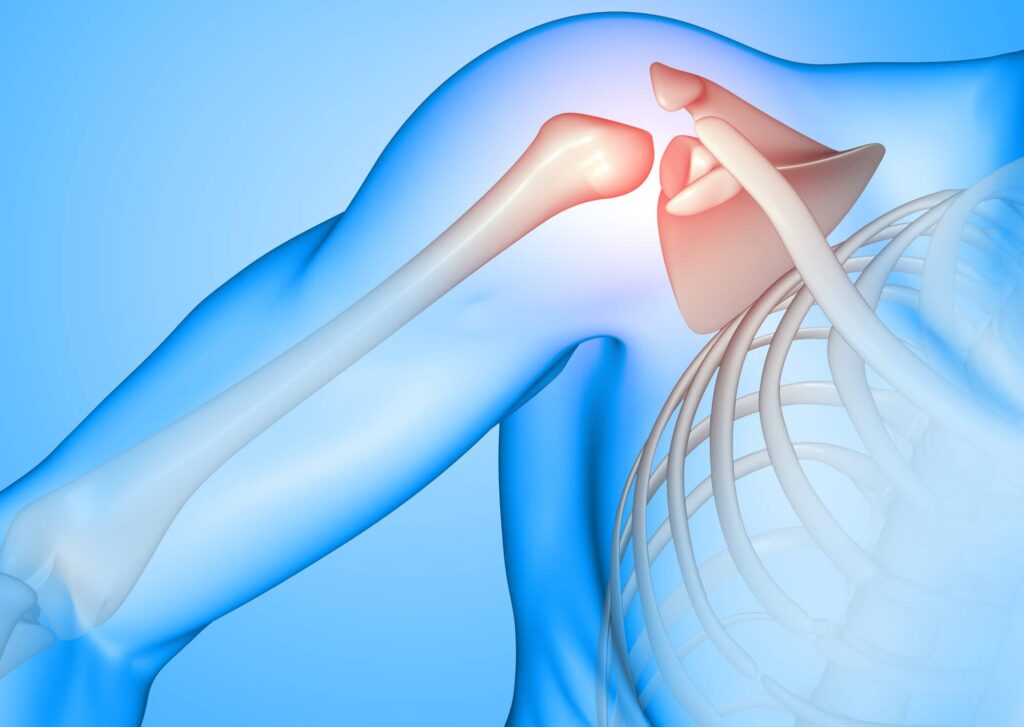

Shoulder Surgery

Shoulder surgery is a medical procedure performed to address various shoulder-related issues, including injuries, chronic pain, and degenerative conditions. The shoulder is a complex joint composed of bones, ligaments, tendons, and muscles that allow for a wide range of motion. However, this complexity also makes it susceptible to a range of injuries and problems that might require surgical intervention

Types of Shoulder Surgery:

Shoulder Arthroscopy

Shoulder arthroscopy is a minimally invasive surgical procedure that allows orthopedic surgeons to diagnose and treat a variety of shoulder conditions using small incisions and a specialized camera called an arthroscope. This technique offers several advantages over traditional open surgery, including shorter recovery times, reduced pain, and smaller scars.

Shoulder arthroscopy is commonly used to diagnose and treat various shoulder conditions, including: